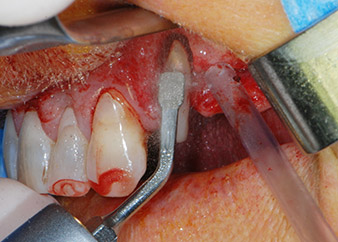

Nous avons toutefois maintenu notre projet initial de conservation des deux dents comme piliers temporaires d'un bridge pendant la période de six mois nécessaire à l'ostéointégration des implants. À la prochaine incision, la situation devrait être réétudiée. Premièrement, afin de gérer le problème endoparodontal, la surface de racine restante a été soigneusement débridée à l'aide d'un équipement piézoélectrique (Piezomed, W&H, utilisé avec l'insert en forme de spatule S1, initialement conçu pour limer la paroi sinusienne latérale) (Fig. 4).

Puis l'apex a été limé à l'aide du même instrument afin d'éliminer les tissus apicaux infectés résiduels et de réduire les éventuelles ramifications des canaux radiculaires (apicectomie) (Fig. 5). Il n'a pas été nécessaire de procéder à une obturation rétrograde car l'obturation orthograde venait juste d'être reprise.